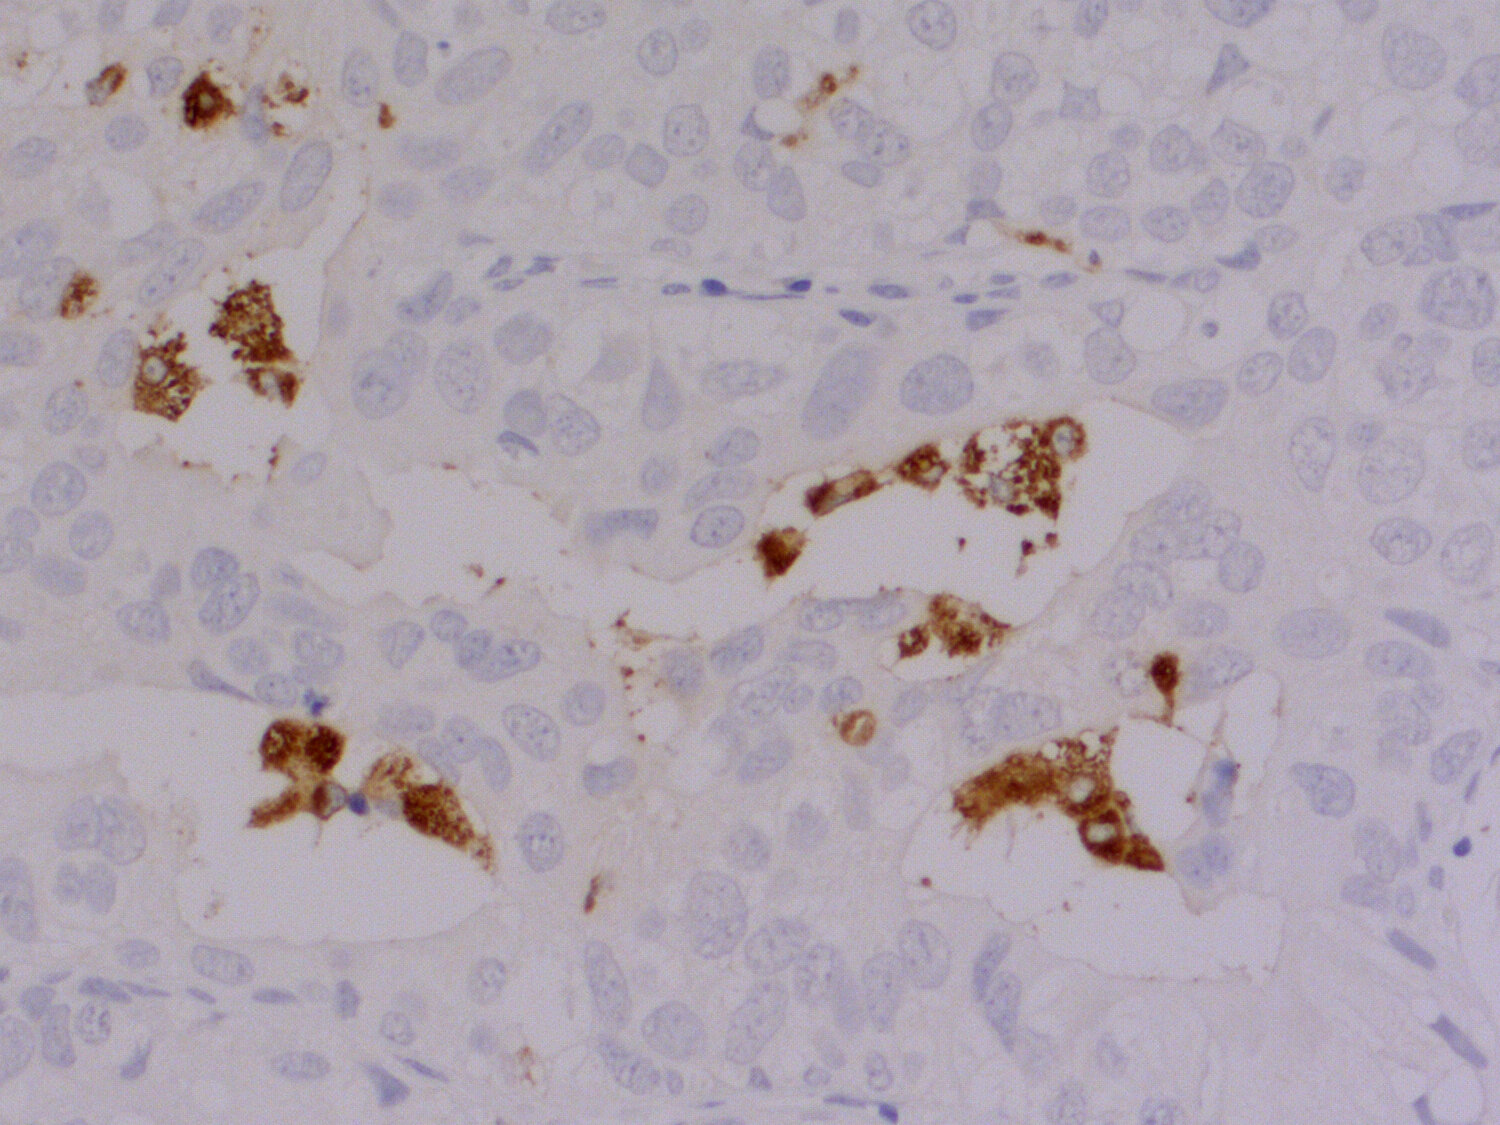

IHC-P (FFPE): 1 : 100 gallery

Immunohistochemistry (IHC-P) of formalin fixed, paraffin embedded (FFPE) tissue (some antibodies require special antigen retrieval steps, please refer to the ”Remarks” section). Immunoreactivity is usually revealed by fluorescence or a chromogenic substrate.

IHC: Antigen retrieval with citrate buffer pH 6 is required.

This product belongs to the HistoSure product line of antibodies developed for and extensively tested in FFPE tissues.

Oncoimmunology (2025) 141: 2546181. HS-460 017 IHC-P (FFPE); tested species: human

Acta neuropathologica (2022) 1443: 589-601. HS-460 017 IHC-P (FFPE); tested species: human